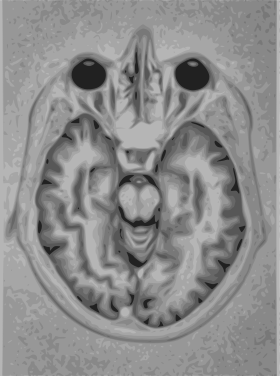

- T1: Cerebrospinal fluid is dark. T1 weighting is useful for visualizing normal anatomy.

T1 (note CSF is dark)

T1 (note CSF is dark) Normal axial T2-weighted MR image of the brain.